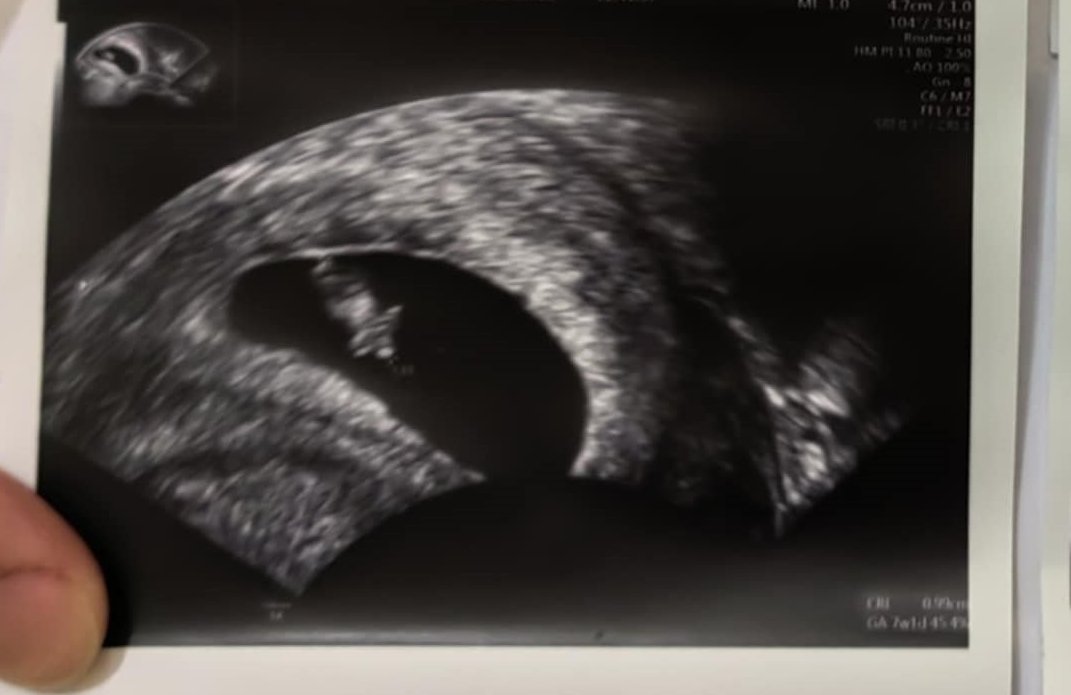

Кога обикновено може да се види ембрионът на ултразвукова снимка?

Какво представлява жълтото тяло на ехографската снимка?